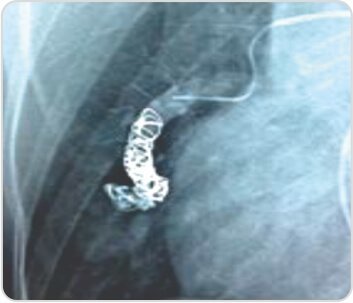

تم تنفيذ سرقة اللف. أظهر تصوير الأوعية الدموية بعد اللف استبعاد 90٪ من تمدد الأوعية الدموية الكاذب من الدورة الدموية. تحسن المريض بعد العملية. أظهر تحليل غازات الدم الشرياني درجة الحموضة 7.430، PCO2-38.5، PO2-64.7، SaO2-87.3 وHCO3-25. بقي المريض بدون أعراض لمدة أسبوعين بعد العلاج بالصمام. ولوحظ ضيق التنفس المجهد والرعاف بسبب التشوه الشرياني الوريدي الثاني وتم تكرار العلاج بالصمام. يظل المريض الآن بدون أعراض لمدة 2 أشهر بعد العلاج بالصمام.

استبعاد 90% من تمدد الأوعية الدموية الكاذب من الدورة الدموية بعد اللف